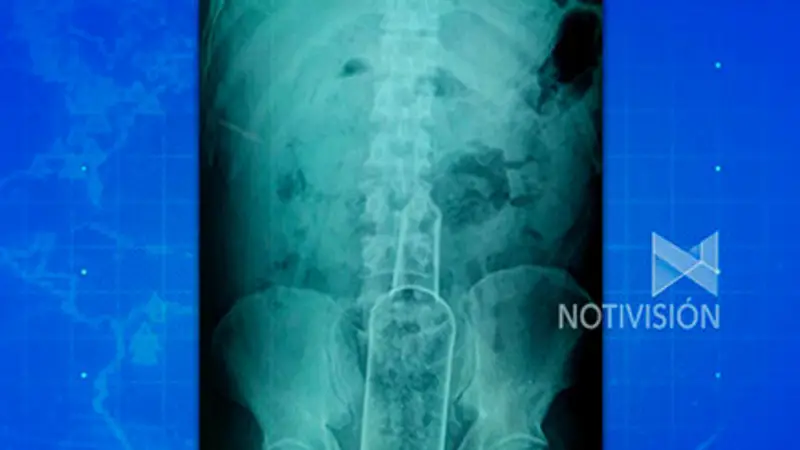

Un hombre de 38 años de edad, llegó en horas de la madrugada el pasado miércoles hasta el hospital El Bajío, ubicado en la zona de La Cuchilla de la capital cruceña, luego de presentar fuertes dolores abdominales y con problemas para caminar. ¿El motivo? tenía una botella de vidrio introducida en el recto.

Carlos Fernando García, médico que atendió al paciente, informó a Notivisión de que el sujeto, que su identidad no se conoce, tenía la botella incrustada en su organismo desde hace tres días, lo que le ocasionó dolores en el estómago y luego fiebre puesto que le era imposible eliminar gases y defecar. Ante ese panorama, el hombre tuvo que ser intervenido de emergencia, ya que se le detectó un traumatismo anal.

La intervención quirúrgica duró al menos una hora, donde en ese lapso los profesionales médicos lograron extraerle el objeto del recto, y una vez afuera, procedieron a lavar los órganos vitales del paciente para que no se contaminaran.